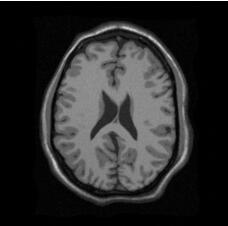

这里展示一下我的mdk文件和保存的png文件